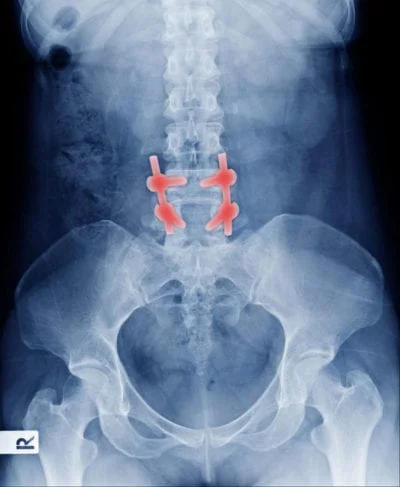

X-ray image of spine surgery hardware